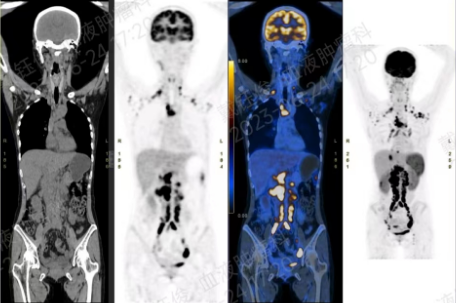

PET-CT示:全身多个淋巴结代谢活跃,考虑淋巴瘤浸润;肝脏S4结节代谢活跃,SUV约11.9,直径约1.6cm;脾脏增大(约7个肋单元)伴弥漫性代谢较活跃,双肾稍肿胀伴局部代谢较活跃,疑淋巴瘤浸润。双侧腮腺区、双颈I-VI区、双锁上、双侧腋窝、纵隔、双肺门、双侧内乳区、右后肋间、隔上、双侧隔脚后、腹腔(胃贲门旁、胃小弯旁、肝门区、脾门区)、腹膜后、双侧路血管旁及双侧腹股沟多个淋巴结放射性浓聚,SUV约32.1,最大约2.1×3.5cm。

2022-7-9 PET-CT